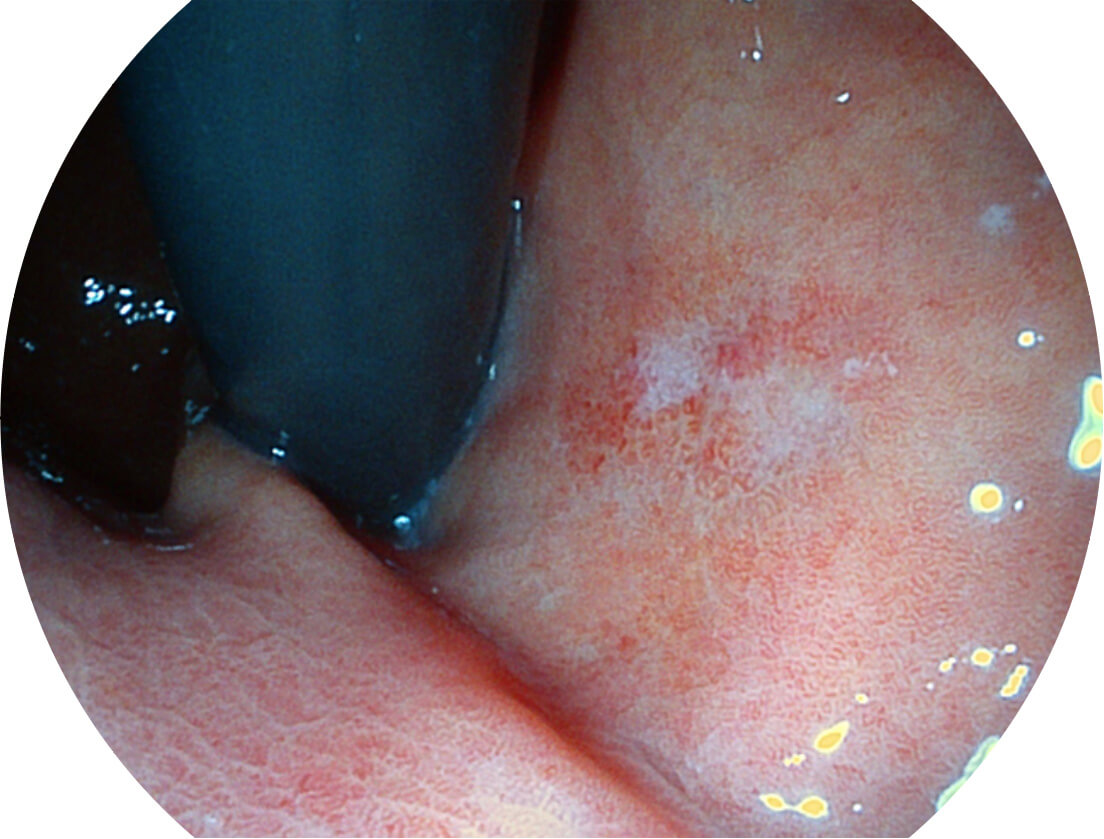

VIST图像

强调浅层黏膜结构的同时,保证照明亮度和提升浅层微血管与中层血管颜色对比度,病变边界更清晰。